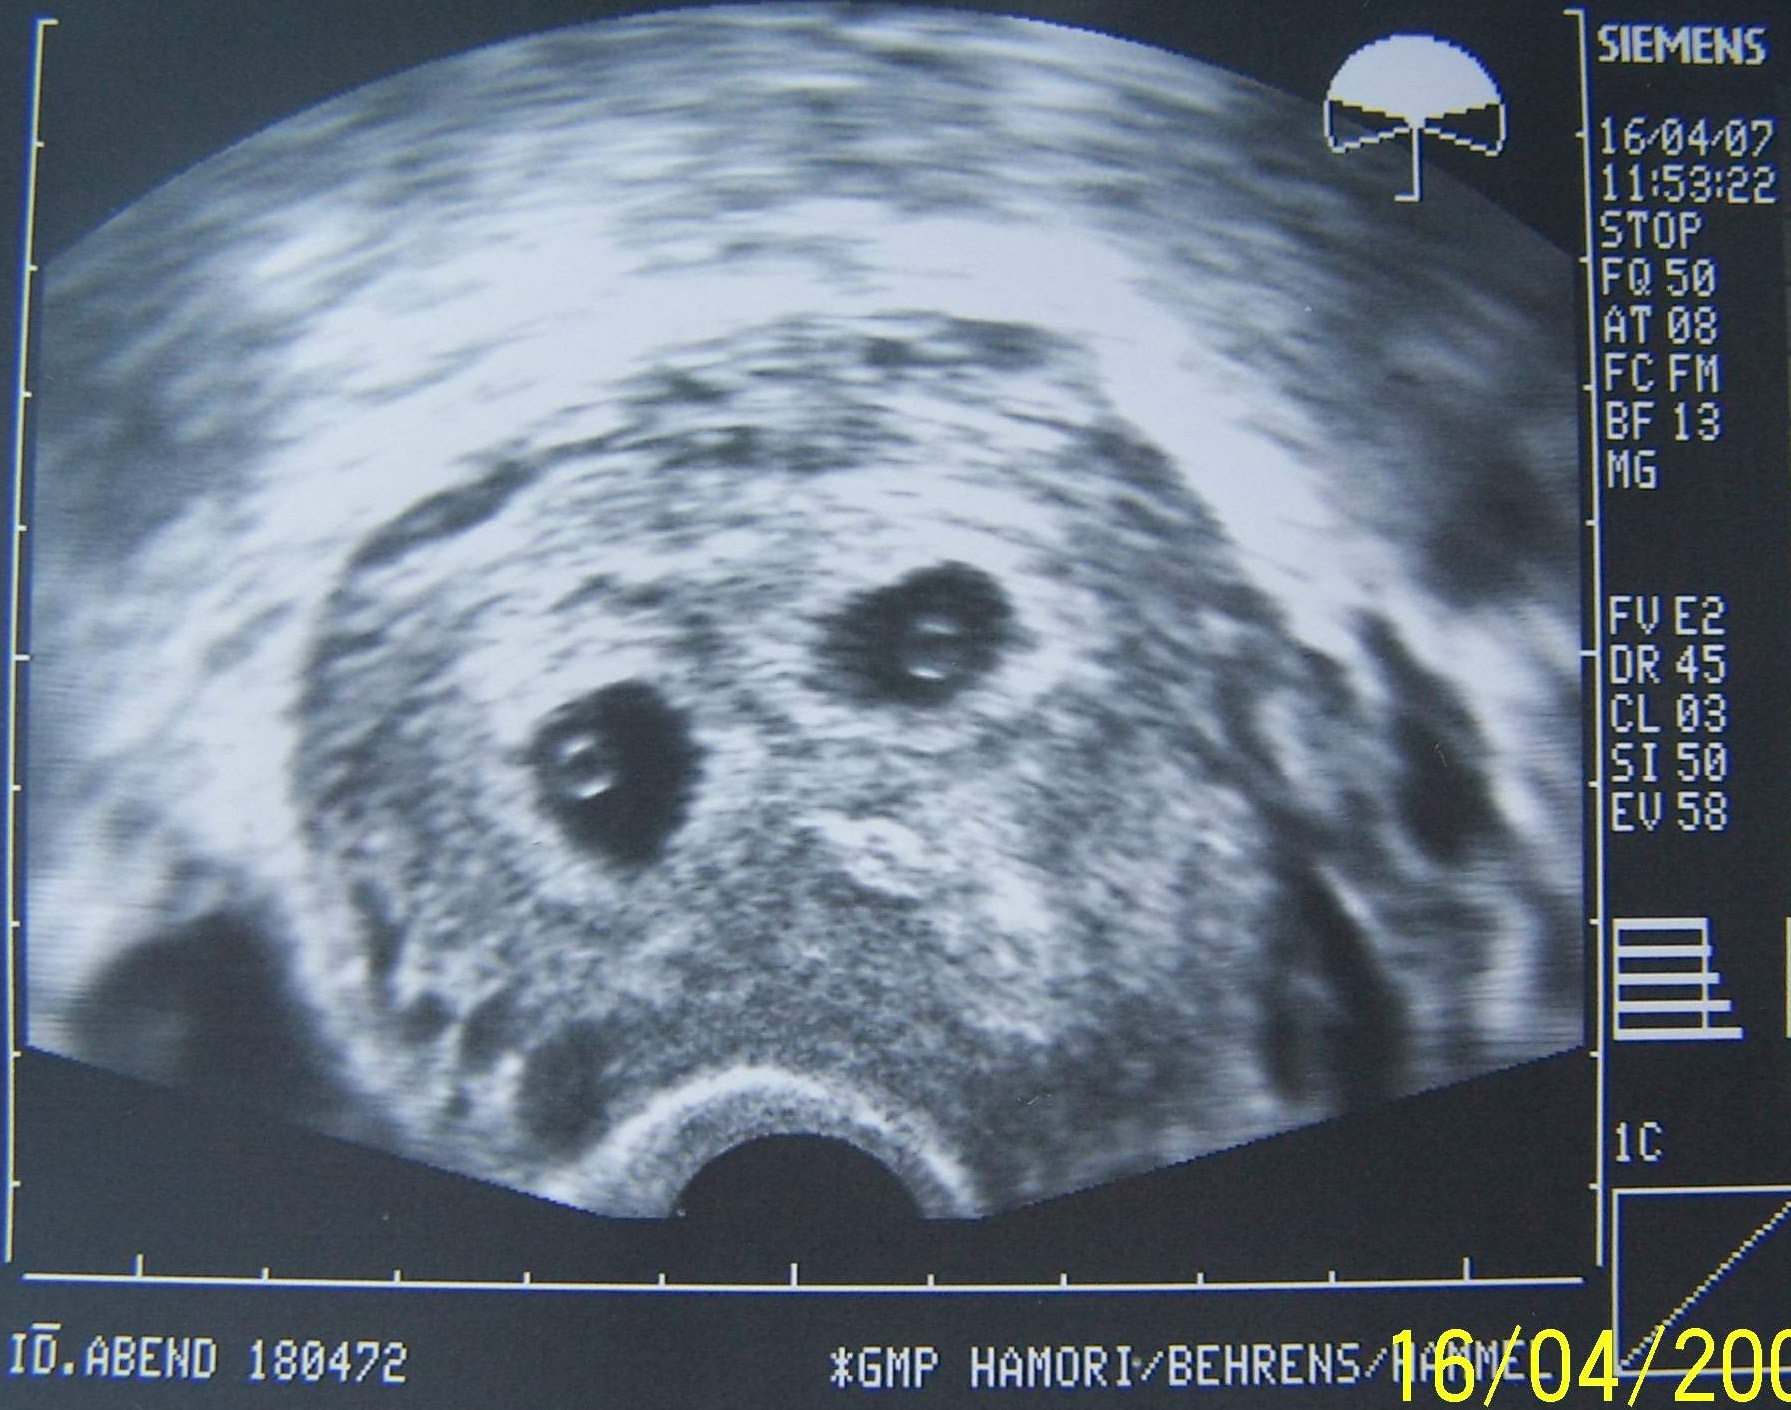

habe. Am DO hab ich noch einen Termin zum US bei Fr. Ha..ch. Das ist meine nächste Etappe